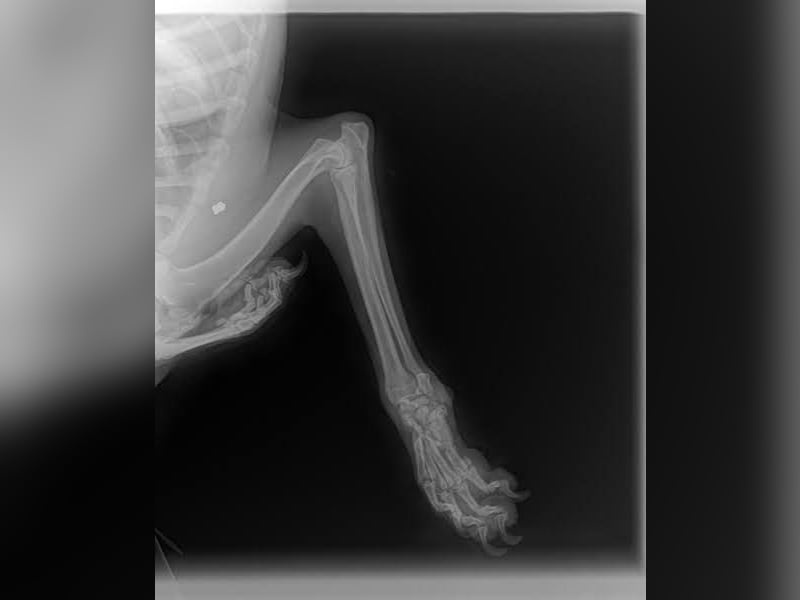

Bemerkungen: Scotti hat Probleme mit seiner Pfote, denn auf ihn wurde geschossen.

Auf Scotti wurde geschossen. Er wurde schwer an der Vorderpfote verletzt und er wurde dann auch einfach liegen gelassen. Glücklicherweise wurde der Tierschutz verständigt und Scotti wurde direkt in ärztliche Obhut gebracht. Dies alles geschah in der zweiten Januarwoche 2025.

Die Genesung von Scotti dauerte sehr lange, aber alle Bemühungen haben sich gelohnt und Scotti hat auch alle Anwendungen brav und geduldig ertragen. Die Verletzung ist aktuell verheilt, aber Scotti wird wohl sein ganzes Leben humpeln.